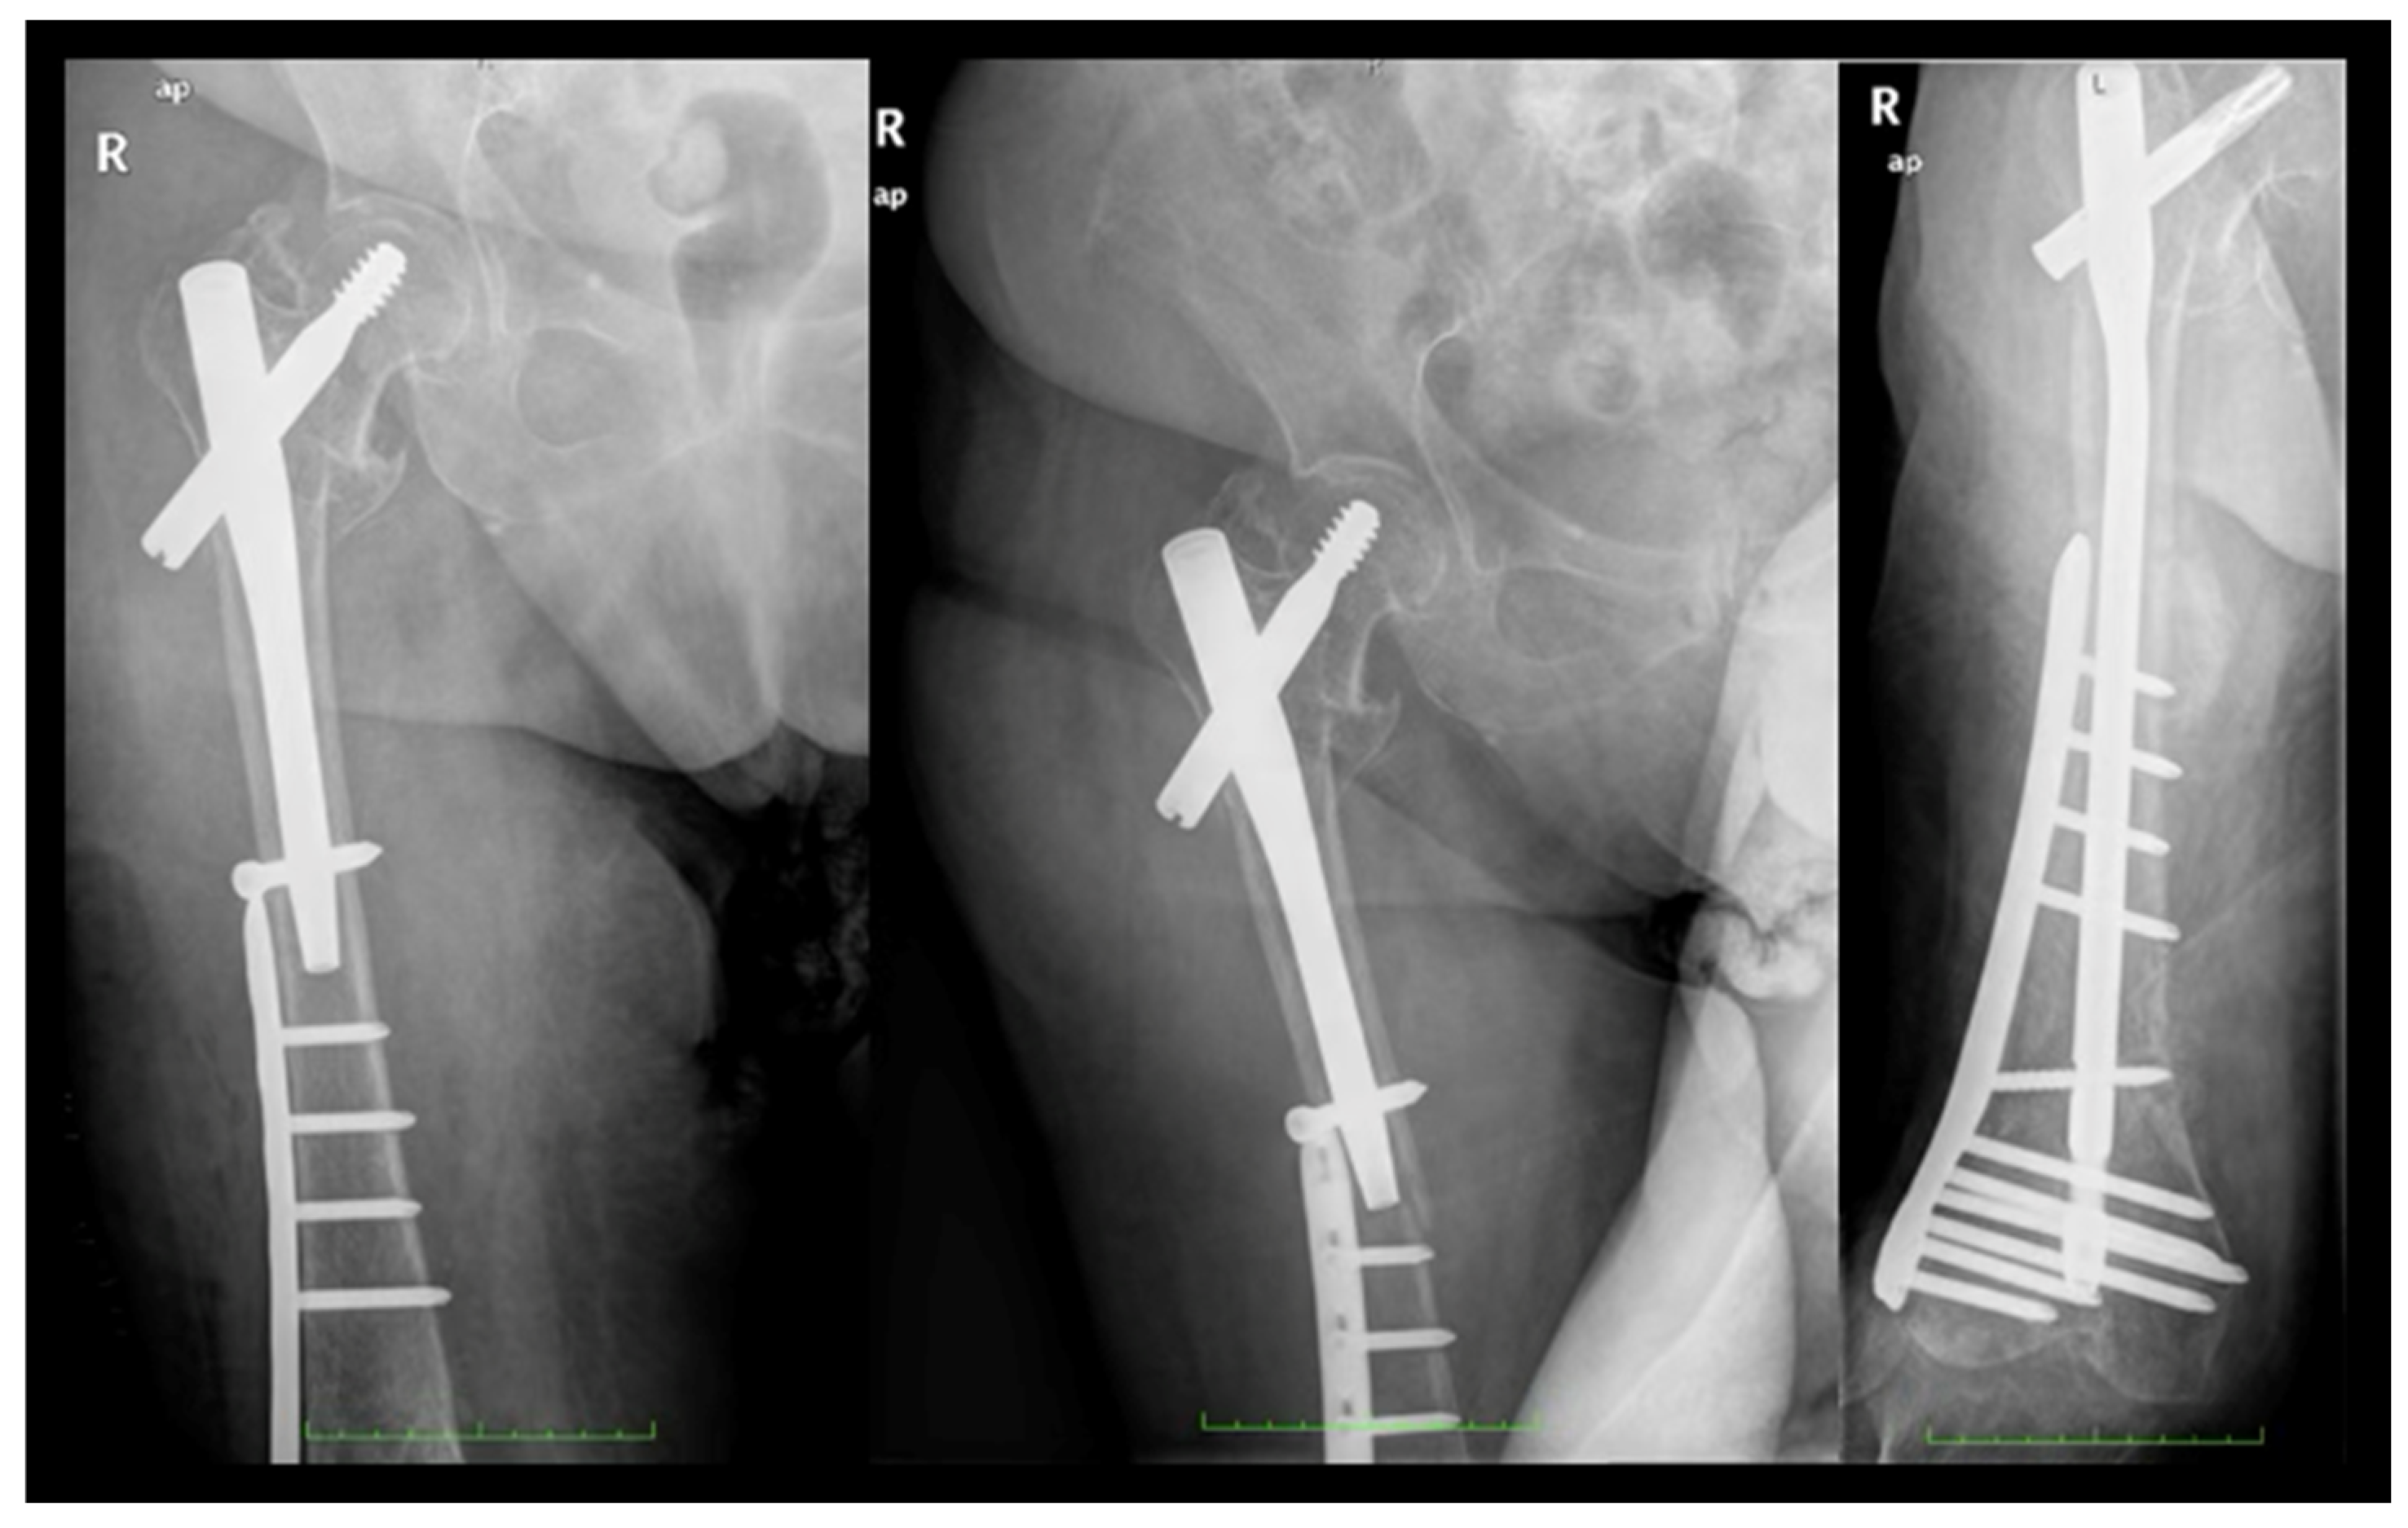

With 26.4% of patients experiencing fractures within 2 months post surgery of the index fracture, we advise a careful surgical technique to further improve outcomes and minimize the risk of PIFFs. The following strategies can be adopted. Surgeons should avoid overtightening distal locking screws against the outer cortical bone of the femur. Utilizing short femoral nails that do not impinge upon the anterior cortical bone (or considering the use of anatomical left and right nails) can also be beneficial. Employing overlapping techniques when other implants are present in the femur is advisable, while preventing the errors and outcomes presented in Figure 4, Figure 5 and Figure 6. Furthermore, using protective medications for bone fragility, such as anti-resorptives, following the diagnosis of an initial fracture (index fracture) may enhance patient outcomes.

Figure 4. Error #1—anterior cortical impingement. Longer versions of short nails (exceeding 200 mm in length) can impinge on the anterior cortex of the femur, creating a stress concentration point at the tip of the nail that may lead to a fracture. To avoid this complication, the use of anatomically designed nails (available in left and right models) or long nails is recommended.